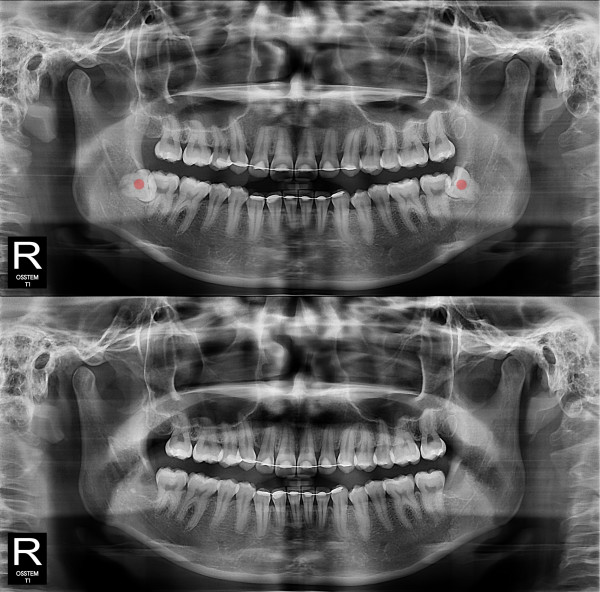

智齿拔除 完全埋伏智齿